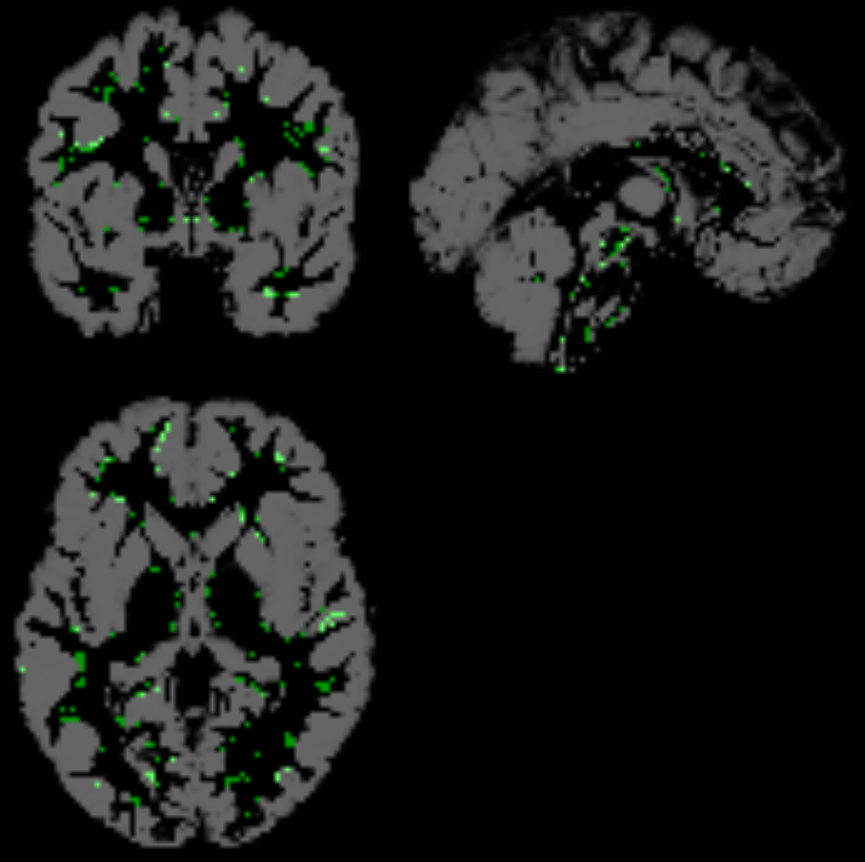

The initial analysis was performed without accounting for the presence of poor quality images, as shown in Figure 5. Their presence can be attributed to errors in the acquisition or pre-processing pipeline, and affects every group randomly. Therefore, the balance in age or center is not affected by excluding them. The impact of incorporating defective images in the region detection process can be assessed by subsequently removing them from the dataset, thereby assessing the overall influence of noisy data.

Refer to caption

Figure 5: Brain mosaics from different centers to assess the presence of defective images. Specifically, the mosaics of three centers with distinct issues in their images are shown:(a) CALTECH’s cerebral mosaic, (b) YALE’s cerebral mosaic and (c) UM_1’s cerebral mosaic.